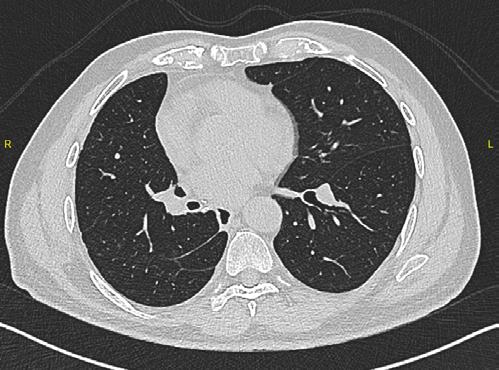

Se realiza cirugía con lobectomía inferior derecha, con resultado histopatológico de tumor carcinoide atípico, se realiza seguimiento con tomografía simple de tórax sin complicaciones en el lecho quirúrgico.

Figura 6. Estudio de seguimiento postlobotomía.